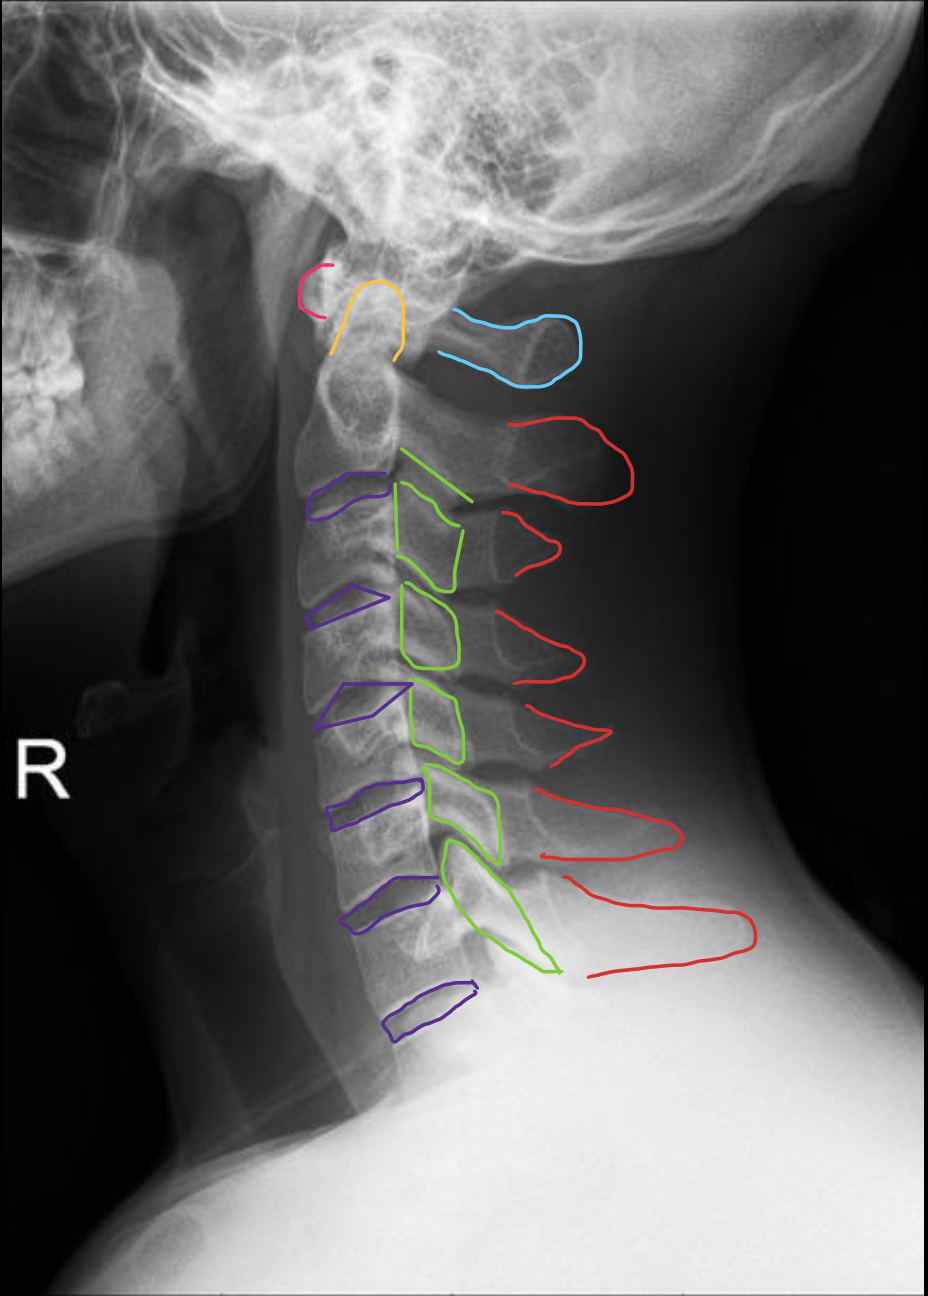

C2

C3

C4

c5

c6

c7

T1

1ST Rib

钩突

Uncinate process

关节柱 / 侧块

Articular pillars

棘突

Spinous process

乳突气房

Mastoid air cells

下颌角

Angle of mandible

椎间隙(Intervertebral Disc space)

IVD space

气管

Trachea

齿状突

Odontoid process C1

颅底

Base of skull

下颌骨

Mandible

寰枢关节

Atlanto-axial

寰椎侧块

C1 lateral mass

枢椎棘突

C2 spinous process

寰椎后弓

Posterior arch C1

寰椎横突

C1 transverse process

C1

寰椎前结节

C1 anterior tubercle

寰椎后弓及后结节

C1 posterior arch & tubercle